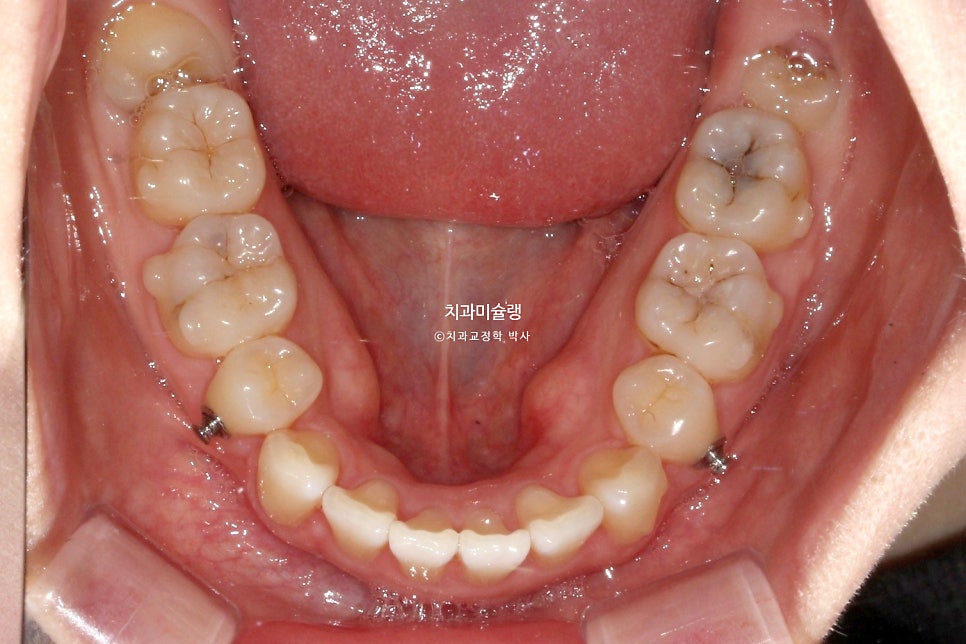

무난하게 70개 장치를 모두 낀 후 모습입니다.

약간의 과개교합이 남아있습니다. 중심선 개선이 더 필요힙니다.

어금니 교합은 좋습니다.

어금니 교합은 물샐틈 없는 1급 교합관계를 보입니다.

발치공간은 깔끔히 마무리 되었습니다.